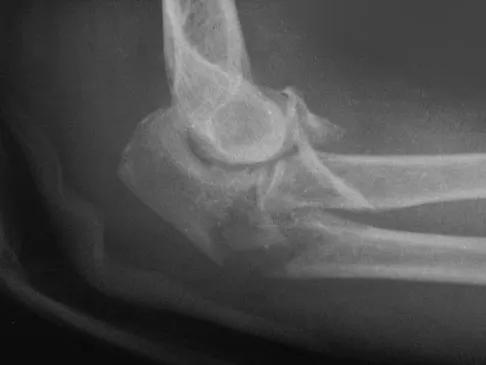

Question 48High Yield

An 11-year-old boy has had a fever and pain and swelling over the lateral aspect of his right ankle for the past 3 days. Examination reveals warmth, swelling, and tenderness over the lateral malleolus, and he has a temperature of 103.2 degrees F (39.5 degrees C). Laboratory studies show a WBC count of 13,200/mm3 with 61% neutrophils, an erythocyte sedimentation rate of 112 mm/h, and a C-reactive protein of 15.7. Radiographs and a T2-weighted MRI scan are shown in Figures 13a through 13c. Aspiration yields 1 mL of purulent fluid. Management should now consist of

Explanation

The initial signs and symptoms of acute hematogenous osteomyelitis vary widely but usually include fever, bone pain, and impaired use of the involved extremity. In lower extremity infections, the child may limp or refuse to walk. Examination often reveals bone tenderness. In more advanced cases, erythema, warmth, and swelling may be present. The WBC and neutrophil counts are not always elevated, but the erythocyte sedimentation rate will be abnormal in more than 90% of patients. When the infection is diagnosed early, before a subperiosteal abscess has formed, antibiotics alone may be adequate to treat the infection. This patient has a more advanced infection, however, with the MRI scan revealing a subperiosteal abscess that was confirmed by aspiration. When an abscess is present, surgical drainage is generally indicated to remove devitalized tissue and to enhance the efficacy of the antibiotics. Further studies, such as bone or indium scans, are not necessary and will delay definitive treatment. Scott RJ, Christofersen MR, Robertson WW Jr, et al: Acute osteomyelitis in children: A review of 116 cases. J Pediatr Orthop 1990;10:649-652.